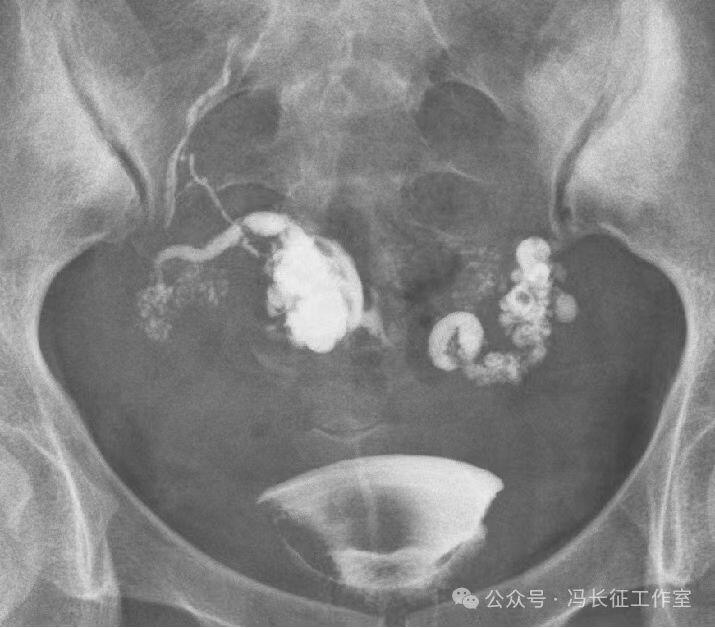

输卵管积水的子宫输卵管造影尽量包括这5个方面的描述,诊断的临床意义才最大,这样才能给好的生殖科医生有价值的建议,帮助给不孕者制定最好的助孕治疗方案。比如这例输卵管积水,峡部结节性输卵管炎(病因),交通性(积水近端是否和宫腔相通),中度(积水大小),厚壁(管壁的厚度),多囊(囊腔的多少)。

微信图片_20240220111200(4).jpg

最后诊断应该是:双侧峡部结节性输卵管炎并双侧中度、厚壁、多囊、交通性输卵管积水。